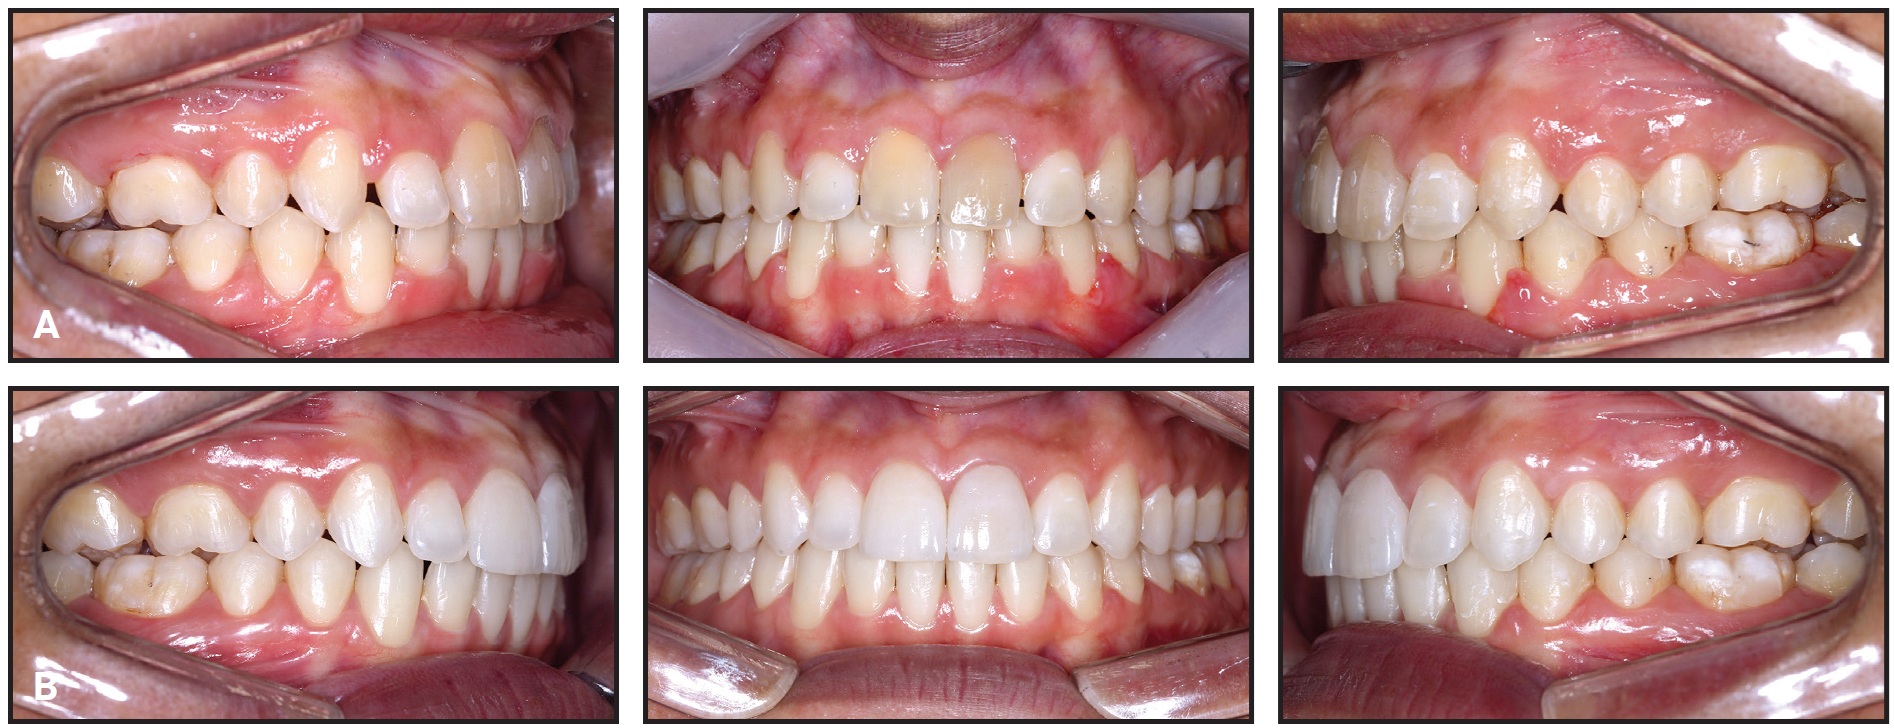

Orthodontic appliances were removed after 14 months of treatment (Fig. 10). The objectives of this phase had been met with the achievement of a functional and balanced occlusion. The patient was referred for gingivoplasty, whitening, and faceting procedures on the upper central incisors.

Fig. 10 A. Patient after 14 months of treatment. B. After gingivoplasty, whitening, and faceting.

While provisional upper central incisor crowns were being made from bis-acryl composite resin (Fig. 11), the posterior intrusion resulting from bone remodeling in this region was evident. Smile esthetics were also notably improved, with good incisor display and correction of the negative torque on the upper posterior teeth.

The patient was checked every six months after treatment. Records taken three years post-treatment verified the stability of the occlusal relationships and facial harmony (Fig. 12).

Fig. 12 Patient three years after treatment.